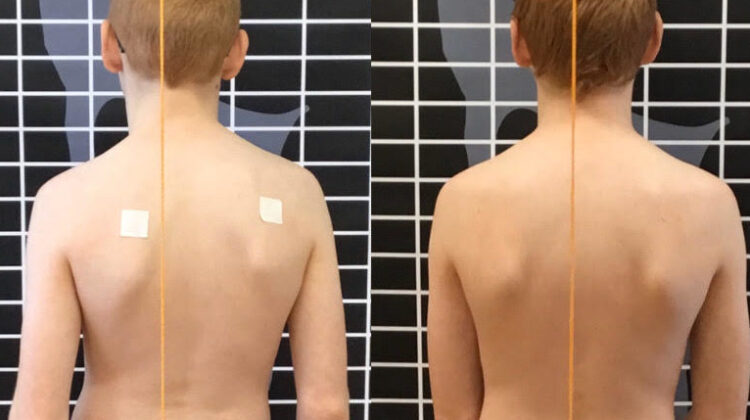

تقليل دوران الجذع (ATR): يقل التواء الجسم، ما يحسن مظهر الظهر عند النظر من الخلف.

دعم الصحة النفسية: رؤية تحسن في شكل الجسم وتقليل الانحناء يرفع الثقة بالنفس لدى المراهقين.